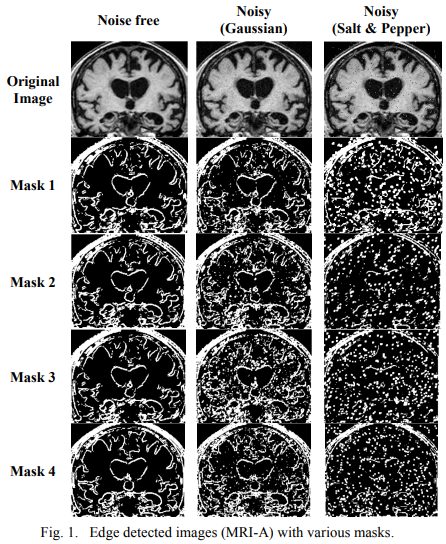

Comparative study of fractional filters for Alzheimer disease detection on MRI images

This paper presents a comparative study of four fractional order filters used for edge detection. The noise performance of these filters is analyzed upon the addition of random Gaussian noise, as well as the addition of salt and pepper noise. The peak signal to noise ratio (PSNR) of the detected images is numerically compared. The mean square error (MSE) of the detected images as well as the execution time are also adopted as evaluation methods for comparison. The visual comparison of the filters capability in medical image edge detection is presented, that can help in the diagnosis of